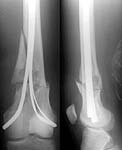

A male 17 years old fallen while usual walking. Images attached combining common and detailed view of the fracture area.

The images show something like a bone cyst. So the question is about preferred method of treatment. Can nailing be an option here? Or we should avoid any touch of the focus and use ex-fix only? Is biosy strongly needed? I would also greatly appreciate any common reference to a systematic review or common guide on surgical management of fractures over cysts, fibrous displasia etc.